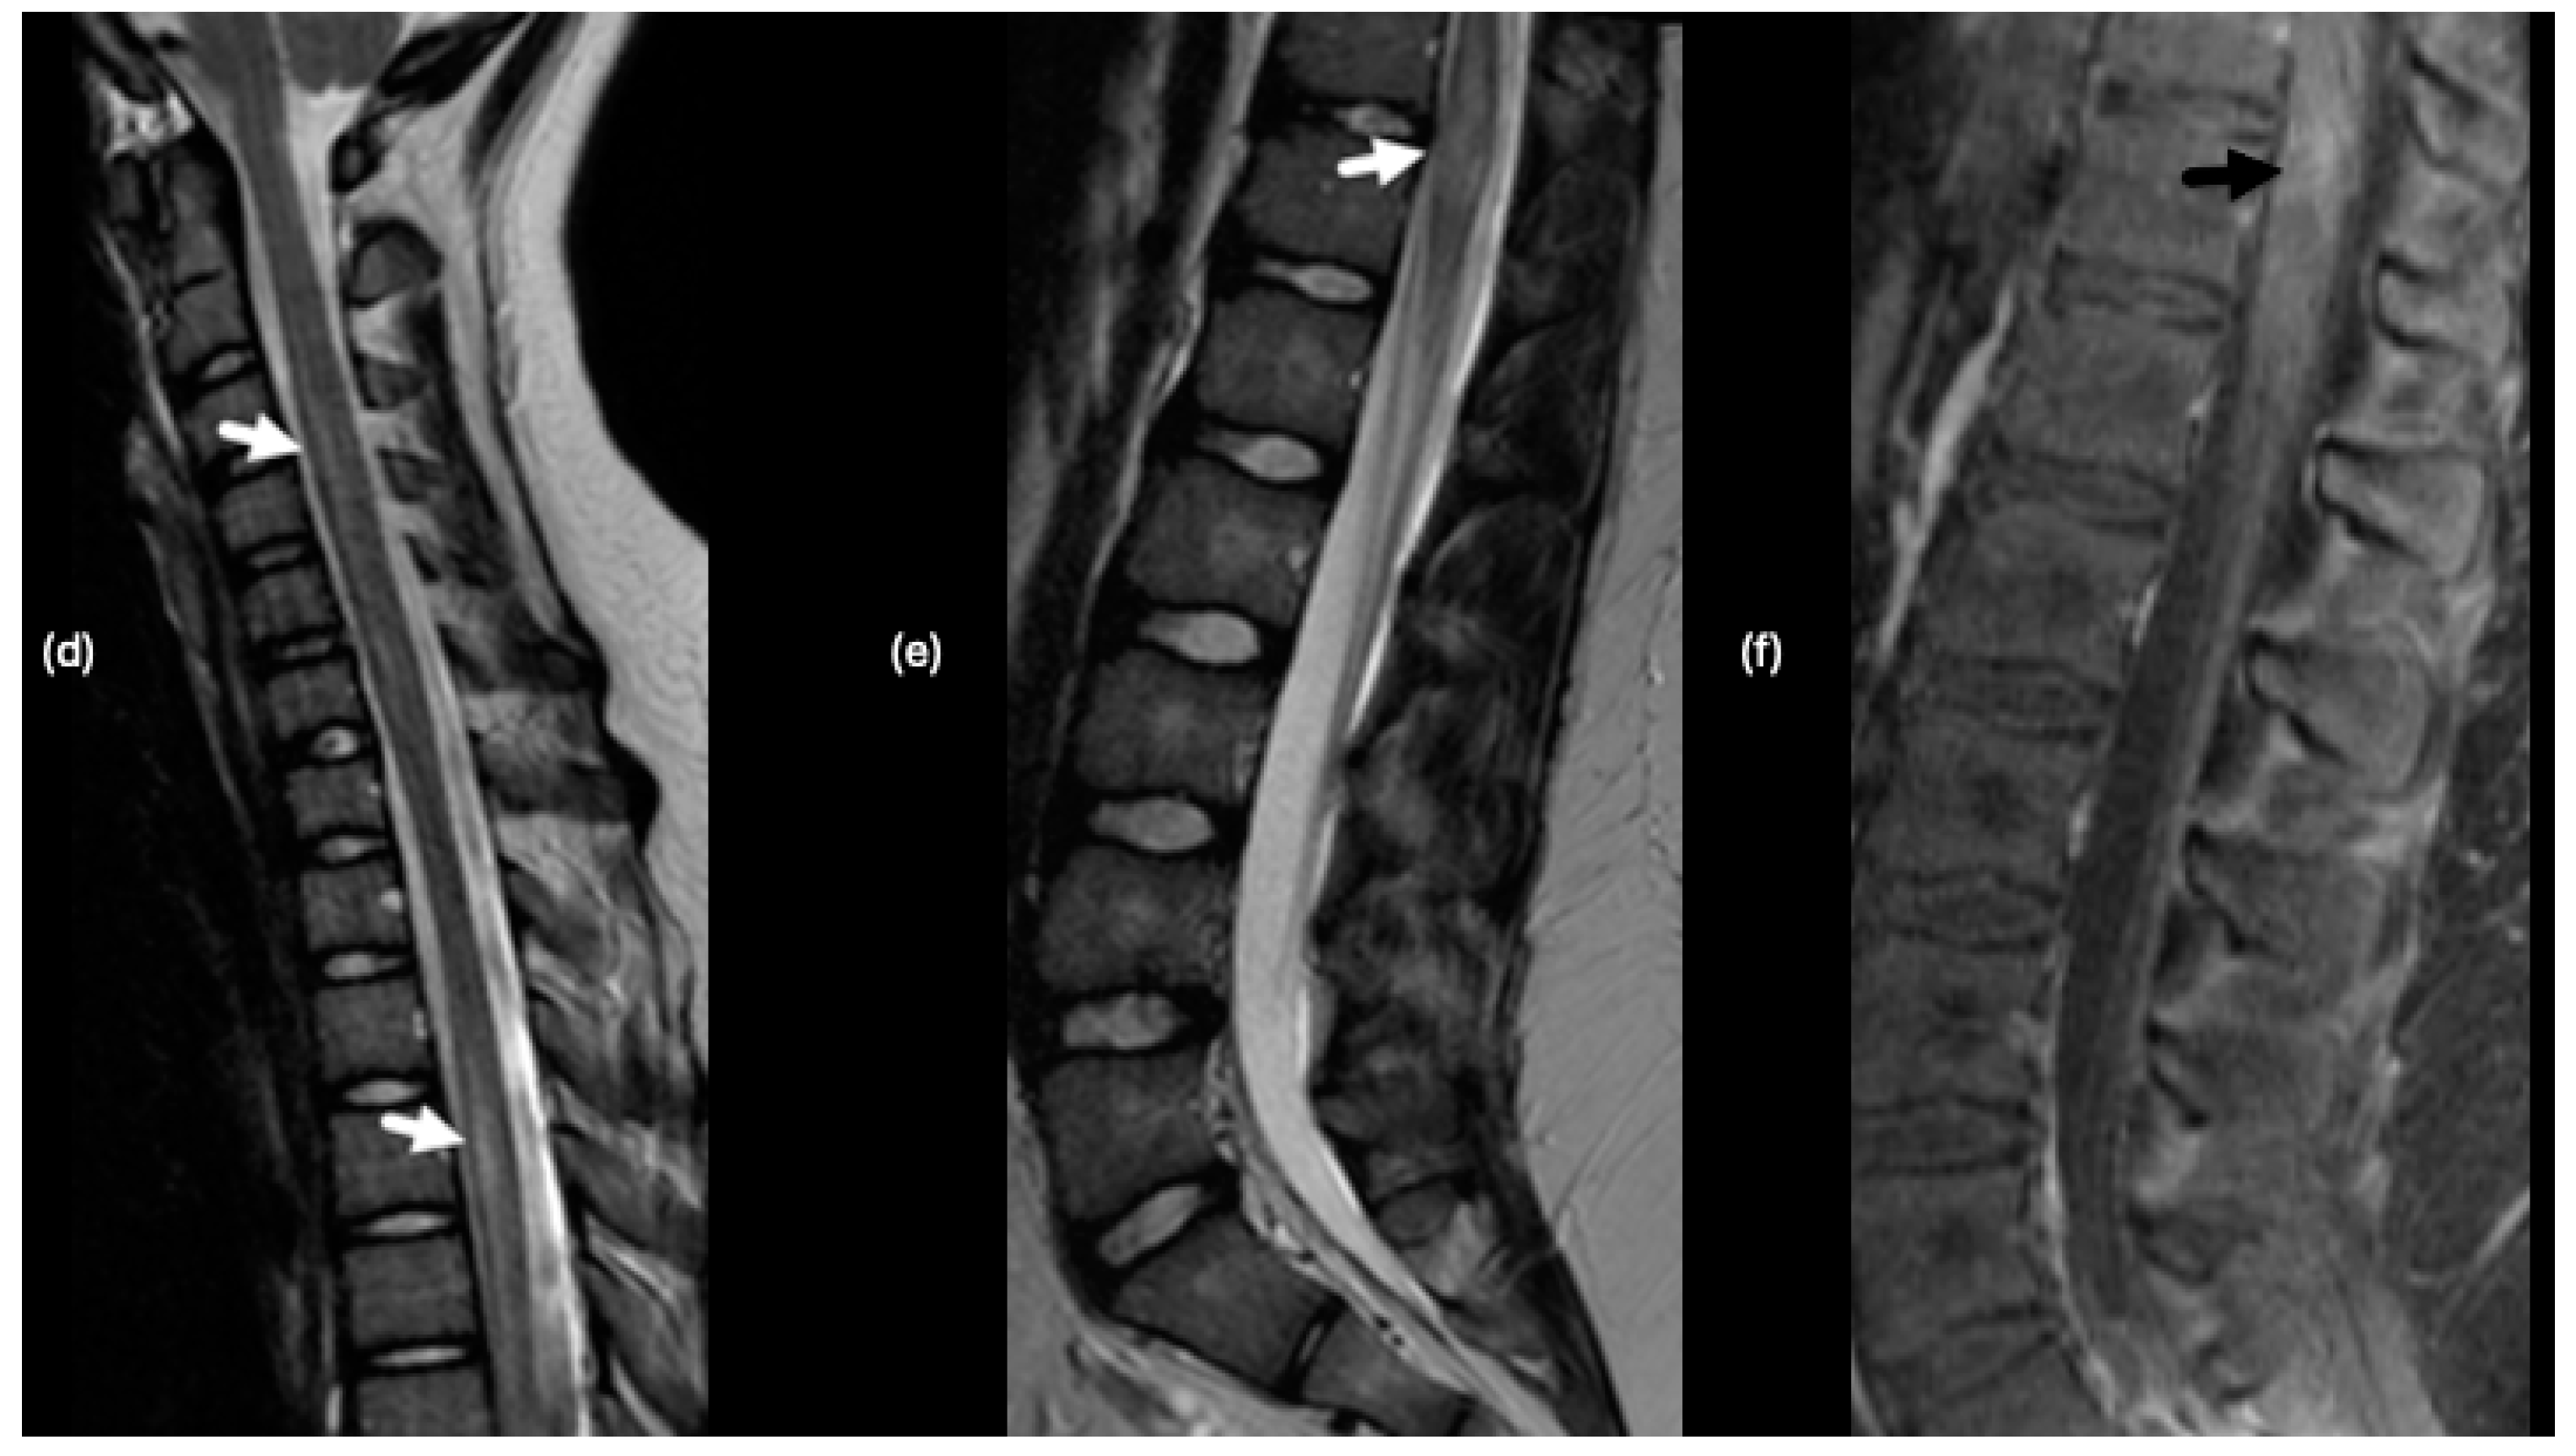

- Tenembaum, S.; Chitnis, T.; Nakashima, I.; Collongues, N.; McKeon, A.; Levy, M.; Rostasy, K. Neuromyelitis optica spectrum disorders in children and adolescents. Neurology 2016, 87, S59–S66. [Google Scholar] [CrossRef]

- Asgari, N.; Skejoe, H.P.; Lillevang, S.T.; Steenstrup, T.; Stenager, E.; Kyvik, K.O. Modifications of longitudinally extensive transverse myelitis and brainstem lesions in the course of neuromyelitis optica (NMO): A population-based, descriptive study. BMC Neurol. 2013, 13, 33. [Google Scholar] [CrossRef] [PubMed]

- Banwell, B.; Shroff, M.; Ness, J.M.; Jeffery, D.; Schwid, S.; Weinstock-Guttman, B.; International Pediatric, M.S.S.G. MRI features of pediatric multiple sclerosis. Neurology 2007, 68, S46–S53. [Google Scholar] [CrossRef]

| NMOSD | At presentation: >60% unremarkable | N/A | N/A | N/A |

| At presentation: <40% with findings | Corpus callosum, subcortical white matter, periventricular white matter, area postrema, brainstem, near the 3rd and 4th ventricles, thalamus and hypothalamus; Spinal cord transverse myelitis | Cloud-like pattern; Linear, pencil-thin of the ependymal surface of lateral ventricles | Corpus callosum lesions-large, irregularly shaped; Tumefactive, confluent lesions->3 cm | |

| NMOSD with ON | At presentation: <40% with findings | Bilateral, longitudinally extensive posterior optic nerves (optic chiasm, optic tracts); spinal cord—central over three or more vertebral segments | Infraorbital fat enhancement | Initial presentation with ON; relapses with transverse myelitis |